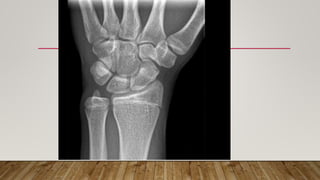

This document discusses radiology and the use of x-rays. It begins with an introduction to radiology and x-rays, noting their importance as the "father of medical investigations." It then discusses anatomy as seen on radiographs and whether x-rays are enough. The document goes on to compare gross views to radiological views, noting what each can and cannot show. It highlights important figures in the development of radiology, from x-rays to CT, MRI, and ultrasound. Specific anatomical structures visible on upper and lower limb x-rays are listed. The document concludes by discussing how pathologies appear on x-rays and the importance of clinical history and knowledge when interpreting radiological images.